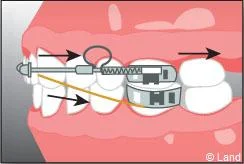

Il s’agit d’un appareil multi-attaches appelé communément « bagues ». Il permet de déplacer très précisément chaque dent. Chaque dent est équipée d’une attache appelée « bracket ». Les dents vont être mobilisées par l’utilisation de fil métallique dont l’alliage, la section, la forme sont déterminés par les différentes étapes du traitement. Ils seront insérés dans les attaches par le biais de ligatures élastiques, métalliques ou d’un mini-clip. Les « brackets » utilisés chez les adolescents sont la plupart du temps métalliques mais ils peuvent être remplacés avantageusement par des éléments transparents ou de la couleur des dents.

Ils sont associés aux bagues et peuvent venir compléter et renforcer l’efficacité de l’appareillage fixe. Il existe des élastiques ou de ressorts qui peuvent aider au déplacement des dents en complément du fil, en servant de guide et des forces extra-orales portées la nuit qui agissent sur des secteurs osseux plus étendus.